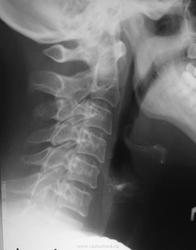

Пол пациента: Женский пол Тип патологии: Врожденная патология Область исследования: Скелетно-мышечная система Методы исследования: Rg Женщина пожилого возраста пришла на снимок ШОП. Сразу заинтересовал второй шейный позвонок. Что может давать такое разрежение костной ткани? https://radiomed.ru/sites/default/files/styles/case_slider_image/public/user/712/sl274633.jpg?itok=8LYUkSO- ID:21360 Чт, 03/05/2012 - 18:15 #1 Nela Не на сайте Был на сайте: 6 лет 3 месяцев назад Зарегистрирован: 12.05.2009 - 20:43 Публикации: 1847 Что-то не вижу я разрежения. Накладываются боковые массы на тело и имитируют "разрежение". А плотность его, если сравнивать в с передним нижним краем С2 и зубовидным отростком, такая же. Чт, 03/05/2012 - 19:02 #2 surgeon23 Не на сайте Был на сайте: 13 лет 9 месяцев назад Зарегистрирован: 25.04.2012 - 17:09 Публикации: 69 Хорошее качество снимков. У пожилой женщины на редкость сохранный позвоночник. перемены - это единственное постоянство, которое нам дано Чт, 03/05/2012 - 19:08 #3 maker4ik Не на сайте Был на сайте: 8 лет 10 месяцев назад Зарегистрирован: 19.10.2011 - 17:49 Публикации: 2682 А где разрежение-то? Стрелочкой тыкните, если не сложно. Чт, 03/05/2012 - 19:17 #4 Глазков Игорь А... Не на сайте Был на сайте: 1 год 1 неделя назад Зарегистрирован: 19.12.2008 - 20:41 Публикации: 1597 Вот и участки разряжения.Приложения: Прийди к Себе Пт, 04/05/2012 - 03:48 #5 Дмитрий86 Не на сайте Был на сайте: 1 год 2 месяцев назад Зарегистрирован: 17.01.2012 - 08:49 Публикации: 285 нормально Пт, 04/05/2012 - 17:50 #6 арти Не на сайте Был на сайте: 12 лет 4 месяцев назад Зарегистрирован: 26.02.2012 - 11:23 Публикации: 490 Для пожилой женщины превосходное состояние шейного отдела Сб, 19/05/2012 - 09:54 #7 maker4ik Не на сайте Был на сайте: 8 лет 10 месяцев назад Зарегистрирован: 19.10.2011 - 17:49 Публикации: 2682 Глазков Игорь Артурович wrote: Вот и участки разряжения. Суммация теней? Пнд, 21/05/2012 - 00:38 #8 Петрович Не на сайте Был на сайте: 7 лет 5 месяцев назад Зарегистрирован: 22.03.2009 - 01:13 Публикации: 3908 Что-то КВО не нравится..., хотя все важные ориентиры черепа срезаны к черту. Неоднозначно всё

Что-то не вижу я разрежения. Накладываются боковые массы на тело и имитируют "разрежение". А плотность его, если сравнивать в с передним нижним краем С2 и зубовидным отростком, такая же.

Вот и участки разряжения.

Суммация теней?

Что-то КВО не нравится..., хотя все важные ориентиры черепа срезаны к черту.